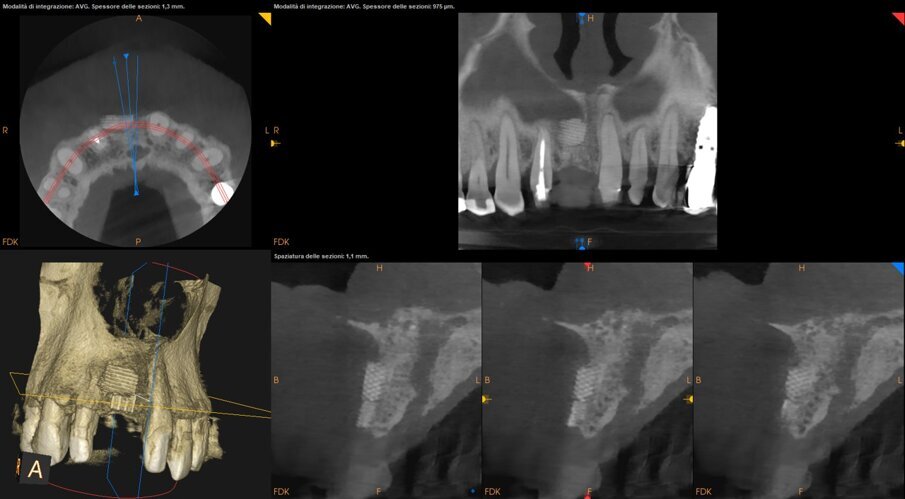

Il paziente era stato precedentemente sottoposto a un intervento di chirurgia rigenerativa con innesto sintetico (stampato in 3D in idrossiapatite/ beta-tricalcio-fosfato) tipo onlay custom-made nella zona dell’incisivo centrale superiore di destra. A 6 mesi dall’intervento, il paziente era pronto a ricevere l’impianto. Per lo studio del caso, il paziente veniva sottoposto a cone beam computed tomography (CBCT) (CS9600, Carestream Dental) (Fig. 1) ed a scansione dell’arcata dentaria di riferimento con potente scanner intraorale (DEXIS IS 3800w, DEXIS) (Figg. 2, 3).

Fig. 1_CBCT (CS9600, Carestream) con field of view (FOV) 10x5 cm dell’arcata rigenerata.

I dati Digital Imaging and Communication in Medicine (DICOM) derivanti dalla CBCT, insieme con il file standard tesselletion language (.STL) ottenuto tramite la scansione intraorale, venivano quindi caricati in cloud in un software di Intelligenza Artificiale (Virtual Patient Creator, RELU). Tali dati venivano elaborati e il software di Intelligenza Artificiale restituiva, in meno di 10 minuti, la ricostruzione 3D della maxilla del paziente, ottenuta tramite segmentazione ossea automatica, accoppiata e allineata alla scansione intraorale (Fig. 4). Il software, inoltre, restituiva la segmentazione di ciascun singolo elemento dentario, sotto forma di files .STL separati, nei quali la corona veniva direttamente dalla scansione intraorale, mentre la radice dalla CBCT (Fig. 5). La “fusione” automatica del dato della CBCT con quello della scansione intraorale, e il perfetto allineamento tra le strutture anatomiche, rappresentava il risultato dell’applicazione dell’Intelligenza Artificiale. La stessa area rigenerata veniva opportunamente segmentata (Fig. 6). A questo punto, l’operatore era in grado di visualizzare tutte le strutture, selezionare quelle interessanti ed esportarle come files .STL. Tali files venivano quindi caricati all’interno di una applicazione dedicata per l’uso per la realtà aumentata (Holodentist, Fifthingenium), insieme con la libreria implantare del sistema scelto (Naturactis, Lyra ETK) per la risoluzione dello specifico caso clinico (Fig. 7). L’operatore vestiva quindi gli occhialini per la Realtà Aumentata (MagicLeap2, Magic Leap) e, anche attraverso l’aiuto di uno specifico joypad, era in grado di pianificare l’impianto in 3D nell’esatta posizione, profondità ed inclinazione, impiegando gli ologrammi (Clicca QUI). Terminata la pianificazione e salvata la posizione dell’impianto, essa veniva esportata e impiegata per disegnare, all’interno di software open-source, un template per una chirurgia guidata statica (Figg. 8, 9). Dal momento che Intelligenza Artificiale e Realtà Aumentata non possiedono ancora le certificazioni per l’impiego clinico, tutti i files erano quindi re-importati all’interno di software radiologico certificato (MIMICS, Materialise) per il controllo della posizione implantare nelle cross-sections radiologiche (Figg. 10, 11).

Fig. 10_Controllo della qualità della pianificazione olografica in software certificato (MIMICS, Materialise).

Fig. 11_La pianificazione viene validata radiologicamente.